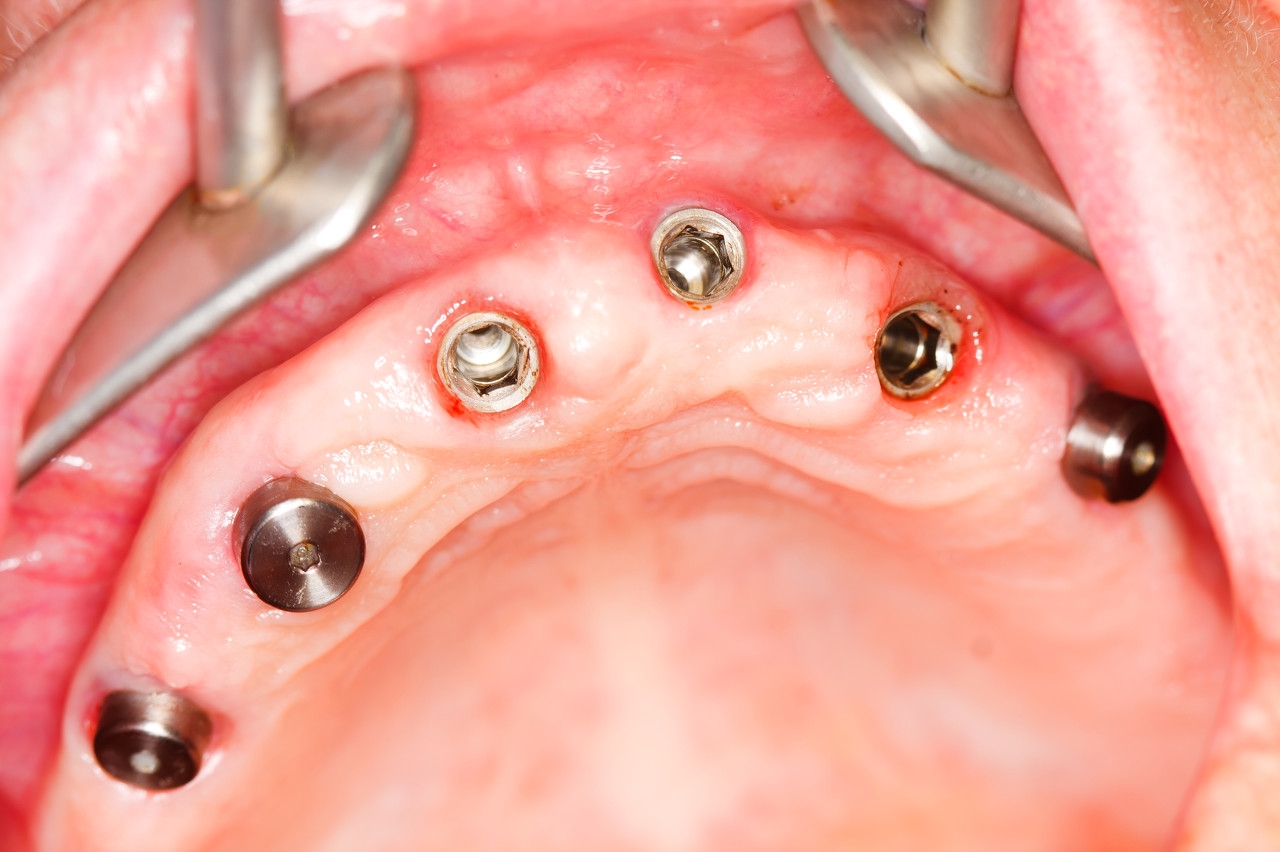

种植牙也叫人工种植牙,并不是真的种上自然牙!而是通过医学的方式,将种植体以外科小手术的方式植入到牙槽骨内!后经过2-3个月,种植体与牙槽骨有一个较好的结合后,再在种植体上戴上牙冠。由于其美观舒适,几乎与真牙相似,故被称为“人类的第三幅牙齿”。

种植牙手术实际是个外科小手术,近似于拔牙!而在手术前都会先打麻药进行局部麻醉,创口小且无痛,术后进食也不会有太大影响。所以大家不用担心怕痛而退缩,及时修复牙齿才是最重要的!